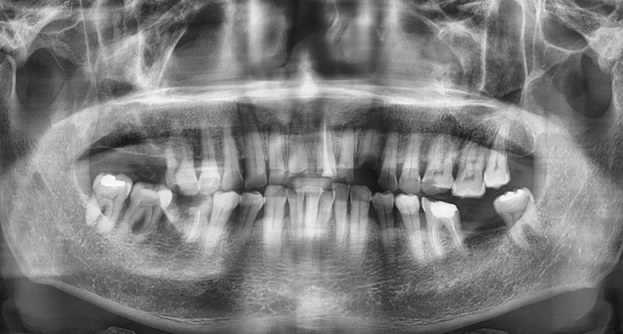

임플란트는 충치나 풍치 치료에서

발치 이후에 나올 수 있는 치료법 중

하나입니다. 위아래 턱뼈에 심은

티타늄으로 제작한 나사를 뿌리 삼아

빠진 자연치아를 대체하는 보철물을

만들어 잇몸뼈 즉 치조골에 삽입하는

방법으로 치아로 고민하는 사람이라면

충치로 인해 치아가 심하게 손상됐거나

치아의 뿌리 부분까지 깨진 경우,

치주염이나 여러 감염으로 잇몸뼈의

소실이 심해 주변 치아가 같이

약해지거나 흔들리는 등 발치 해야

하는 상황이 생길 수 있습니다.